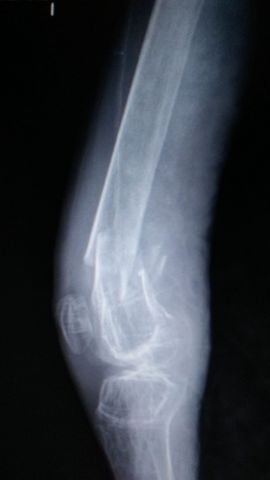

Fractura de húmero, intensa desviación de fragmentos